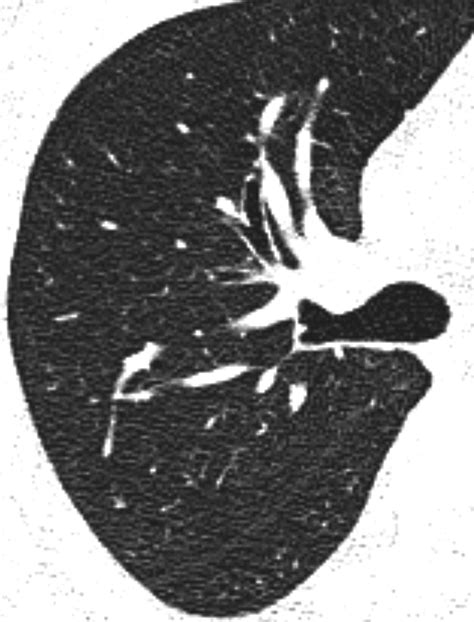

A Ground Glass Nodule is a type of lung nodule that appears as a hazy, increased opacity on a CT scan, without obscuring the underlying bronchial structures or vessels. This distinctive appearance sets GGNs apart from solid nodules, which completely obscure the underlying lung tissue. GGNs can be further classified based on their size and attenuation characteristics, which help in determining their potential malignancy.

• CT Scan: High-resolution CT scans are the primary imaging tool used to detect and characterize GGNs. These scans provide detailed images of the lung tissue, allowing radiologists to assess the size, shape, and attenuation of the nodule.